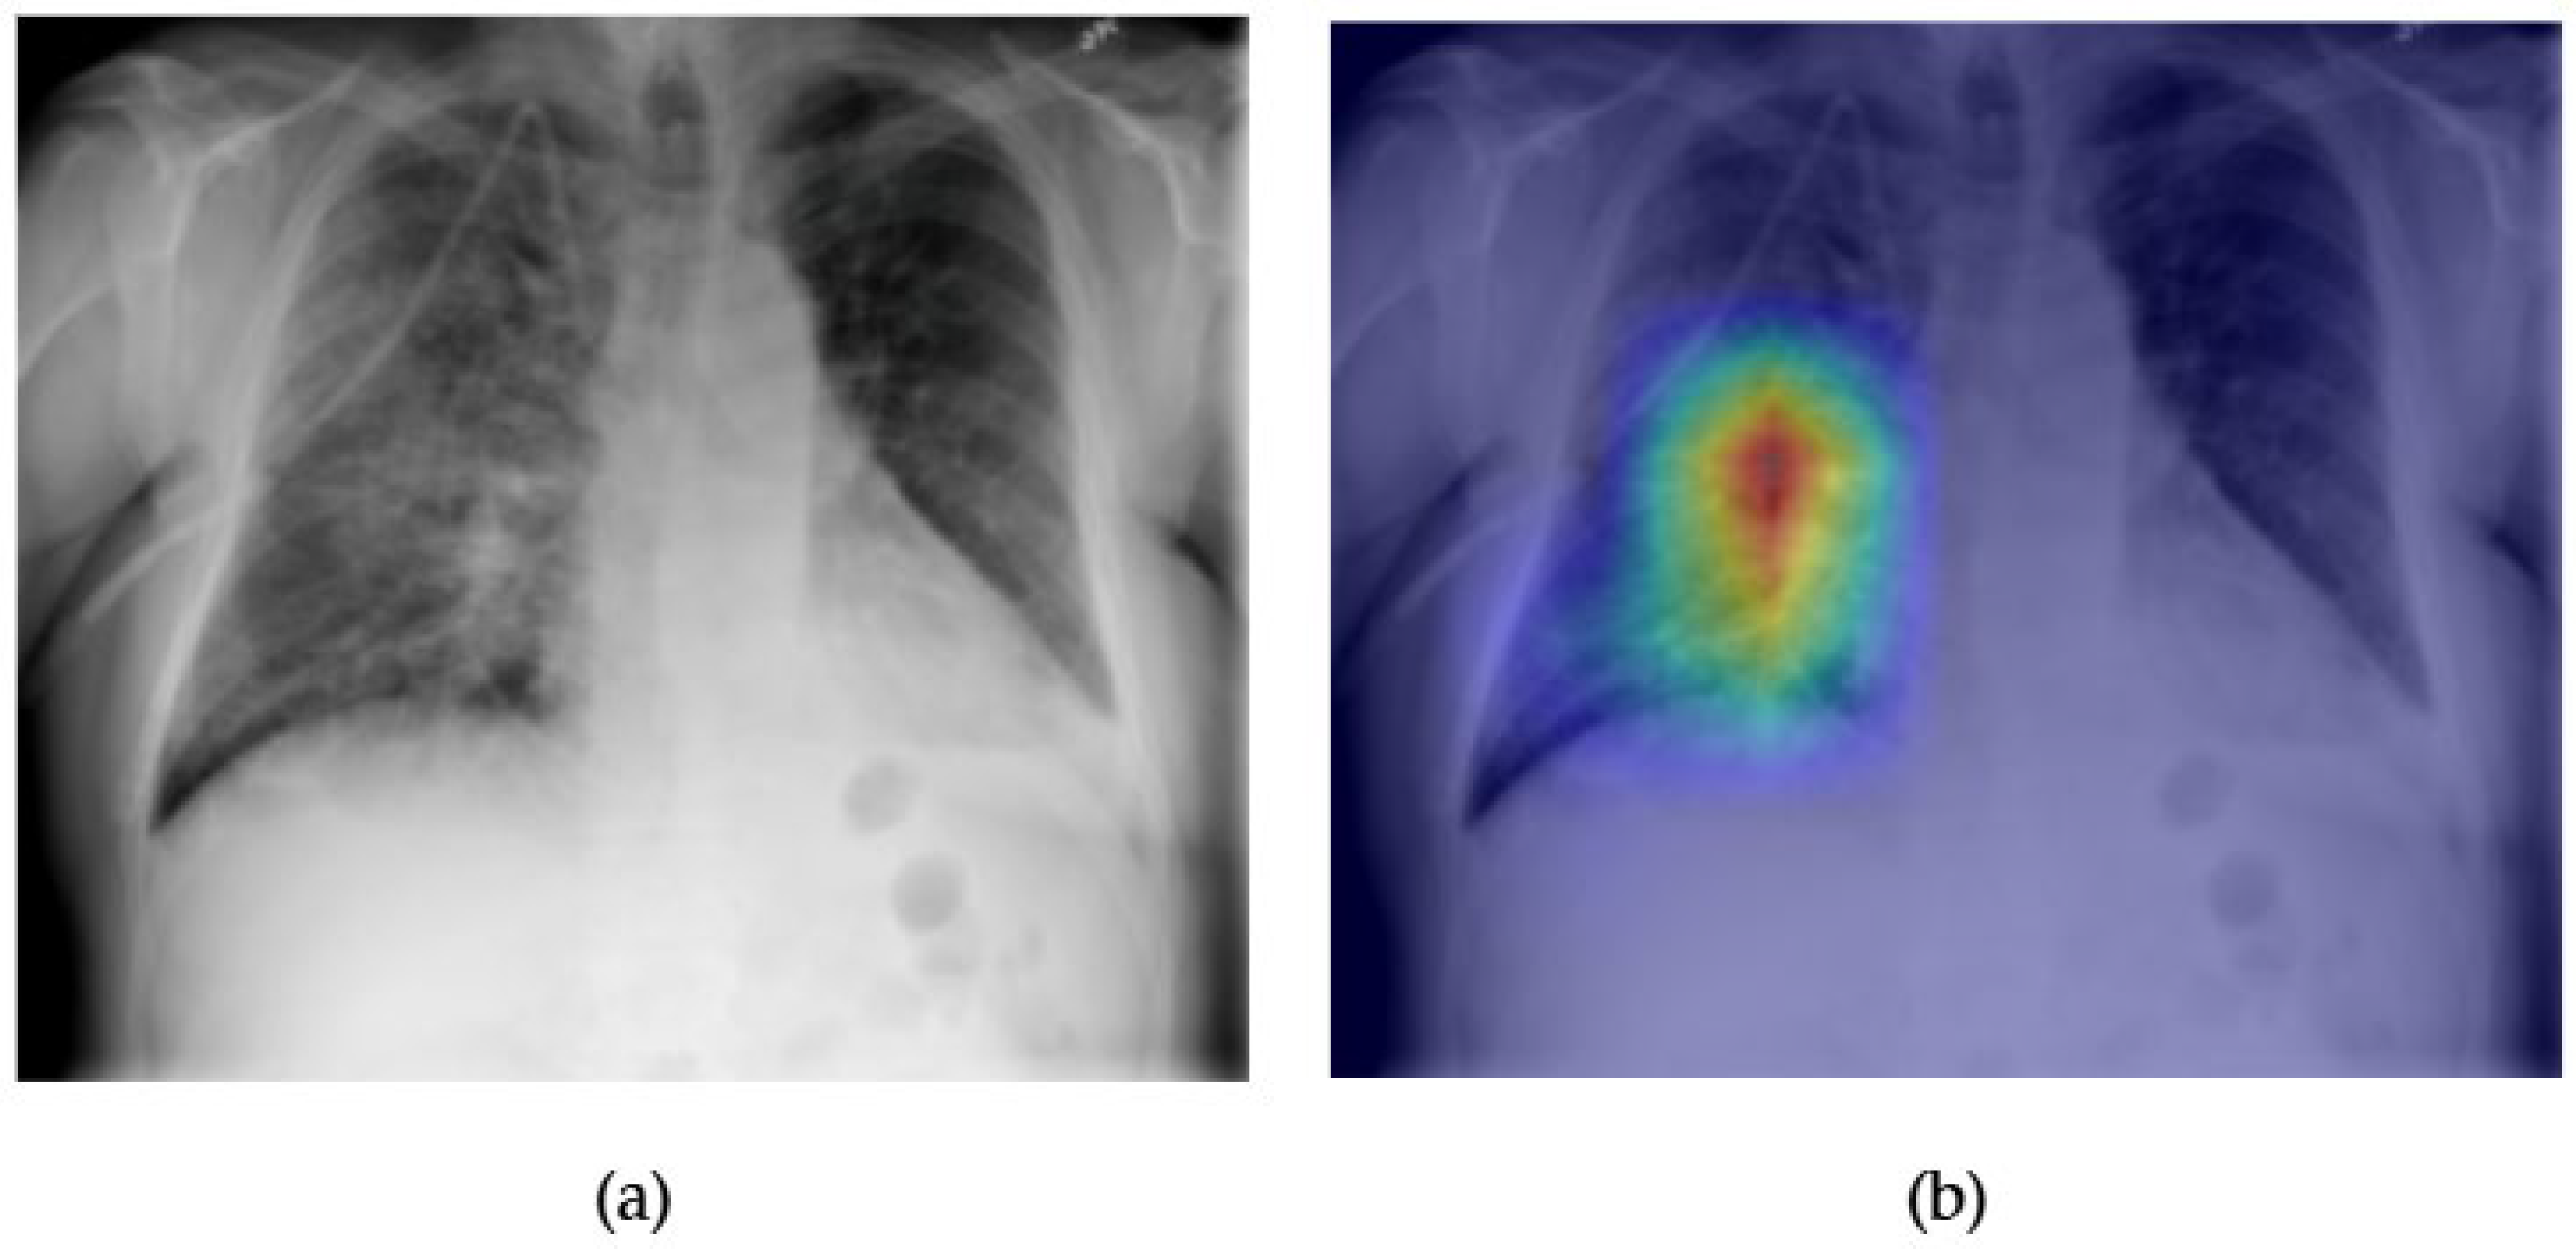

- Although our Grad-CAM-based explainability provides useful localization cues, it is inherently limited by its post hoc nature and reliance on gradient flow from the final convolutional layers. Future research could incorporate advanced interpretability techniques such as Layer-wise Relevance Propagation (LRP), Integrated Gradients, or attention rollouts in Transformers, which may offer a more complete understanding of model reasoning.